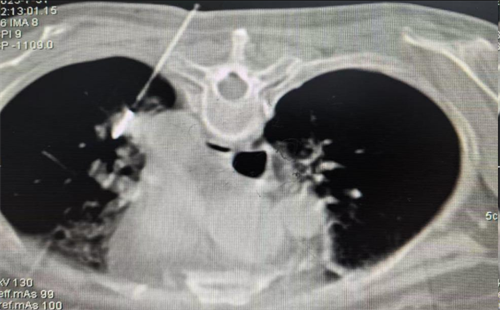

术中精准定位肺转移瘤位置

消融范围完美覆盖肺部病灶